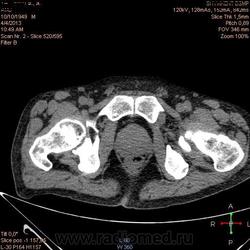

Здравствуйте, коллеги.Помогите разобраться.Пациент 1949 г беспокоять боли в животе , отсутствие аппетита, похудание .За неделю пожелтел, ослаблен.Нужно исключит кацер головки подж.железы.Анализы сегодня сдал еще не готовы.УЗИ зак увеличение л\узлов у ворот печени.Образов головки подж.железы ?На КТ жировой гепатоз.вроде головка подж железы не увеличены.

Мне надо исключить или поставить образование головки подж.железы.Хирурги ждут заключение, хотять оперировать.

Даже если вы пропустили малый рак панкреас, пациент умер не из-за него - желтуха не механическая, а, вероятней, паренхиматозная.